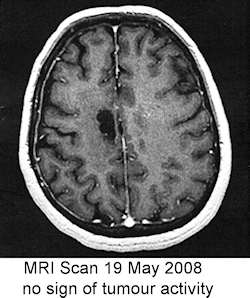

April 2007 - Balance problem and dragging leg. Doctors initially think problems are associated with drugs being used to treat rheumatoid arthritis. MRI scan reveals tumour. Kath becomes unable to walk.

glioblastoma multiforme3 May 2007 - Surgeon says he can operate - but treatment will only be palliative. If nothing is done, Kath will be dead within two months. The tumour is about 3cm round and right in the middle of her head.

15 May 2007 - Got definitive diagnosis of grade 4 glioblastoma multiforme. Just about the worst news it could be. Immediate prospect for Kath is 6 weeks of daily radiotherapy and chemotherapy. After that it will at some stage start to grow again